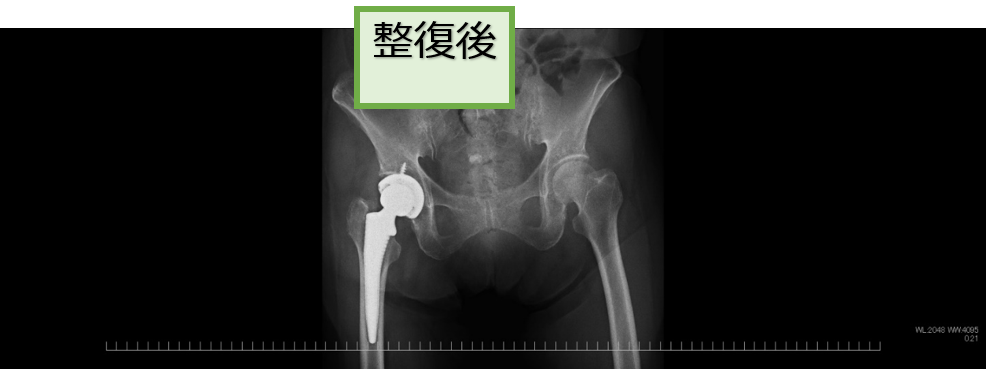

●脱臼の整復

脱臼した部分(肩や股関節など)をリアルタイムに観察しながら元の位置に戻す(整復術)治療です。この治療は整形外科医師が行います。

股関節脱臼に対する整復

右肩関節脱臼に対する整復